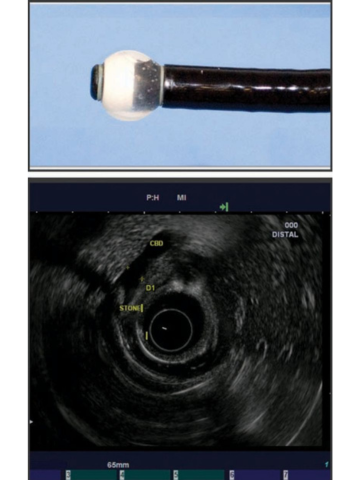

Існує два типи широко використовуваних ехоендоскопів, кожен з яких відрізняється своїми характеристиками. Радіальний ЕУЗД був першим, який був розроблений з забезпеченням 360-градусного огляду в площині, перпендикулярній до осцилографа, подібно до зображення комп’ютерної томографії (КТ) (мал. 2). Лінійне ехоендоскопічне ультразвукове дослідження забезпечує локалізоване косе зображення, паралельне ендоскопу, і дає змогу проводити терапевтичну діагностику ультразвуком (мал. 3). Також доступні високочастотні мінідатчики ЕУЗД, які можна пропускати через стандартний біопсійний канал ендоскопа у випадках, коли структури неможливо пройти за допомогою стандартного ендоскопа.